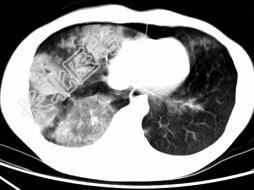

- 单项选择题男,28岁, 外伤后1小时行胸部CT如图,其最可能的诊断为 ( )

E、双肺挫伤